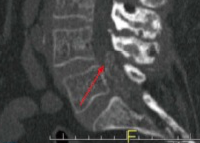

World J Orthop. 2016 Nov 18;7(11):766-775. Spinal Gout: A Review With Case Illustration Hossein ElgafyXiaochen LiuJoseph Herron

Abstract Aim: To summarize clinical presentations and treatment options of spinal gout in the literature from 2000 to 2014, and present theories for possible mechanism of spinal gout formation. Methods: The authors reviewed 68 published cases of spinal gout, which were collected by searching "spinal gout" on PubMed from 2000 to 2014. The data were analyzed for clinical features, anatomical location of spinal gout, laboratory studies, imaging studies, and treatment choices. Results: Of the 68 patients reviewed, the most common clinical presentation was back or neck pain in 69.1% of patients. The most common lab

oratory study was elevated uric acid levels in 66.2% of patients. The most common diagnostic image finding was hypointense lesion of the gout tophi on the T1-weighted magnetic resonance imaging scan. The most common surgical treatment performed was a laminectomy in 51.5% and non-surgical treatment was performed in 29.4% of patients. Conclusion: Spinal gout most commonly present as back or neck pain with majority of reported patients with elevated uric acid. The diagnosis of spinal gout is confirmed with the presence of negatively birefringent monosodium urate crystals in tissue. Treatment for spinal gout involves medication for the reduction of uric acid level and surgery if patient symptoms failed to respond to medical treatment.